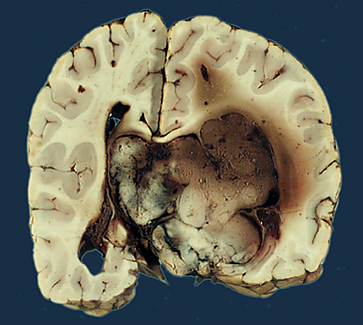

| Макропрепарат хориоидпапилломы | |

Макроскопически опухоль представляет собой округлый узел с мелкозернистой или ворсинчатой поверхностью. Иногда при наличии капсулы поверхность новообразования гладкая. На разрезе ткань серо-розовая, мелкозернистая, несколько плотнее ткани здорового мозга. В ряде случаев содержит гладкостенные кисты с серозным, слизеподобным или кальцифицированным содержимым[1].